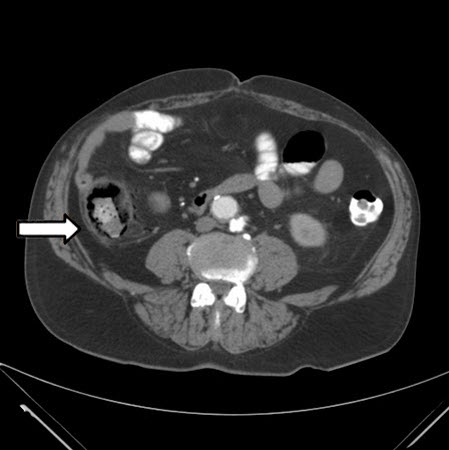

Aneurisma da aorta abdominal: tomografia computadorizada (TC) de um aneurisma da aorta abdominal roto

University of Michigan, mais especificamente os casos do Dr. Upchurch, representando os Departamentos de Cirurgia vascular e Radiologia